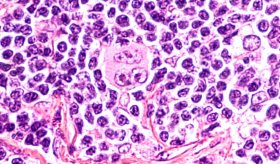

Ahora bien, según las características microscópicas y los signos y síntomas presentados por el paciente, las leucemias pueden clasificarse como agudas o crónicas. En el caso de las leucemias agudas, como su nombre lo dice, se manifiesta de forma aguda, es decir que en corto tiempo el paciente refiere síntomas como fatiga, fiebre, sangrados, dolor articular, entre otros, ya que las células se multiplican con mucha rapidez dando lugar a formas inmaduras, lo cual puede definirse gracias a sus características estructurales. Por otro lado, hablamos de una leucemia crónica cuando las células cancerosas han madurado parcialmente y en estructura, puede decirse que se asemejan más a una célula sanguínea normal, aunque no del todo, por lo que no ejercen adecuadamente su función. Adicionalmente, en cuanto al curso de la enfermedad, las leucemias crónicas suelen ser más lentas, por lo que los pacientes pueden vivir muchos años con la enfermedad sin notar ningún síntoma. No obstante, las leucemias crónicas suelen ser más retantes a la hora del tratamiento.

Por último, la clasificación histológica de cada una de las leucemias dependerá de su línea celular de origen dividiéndose en linfocítica o mieloide, que a su vez se distinguen entre sí por otros factores como edad de presentación, genes asociados, signos y síntomas característicos e incluso, pronóstico.